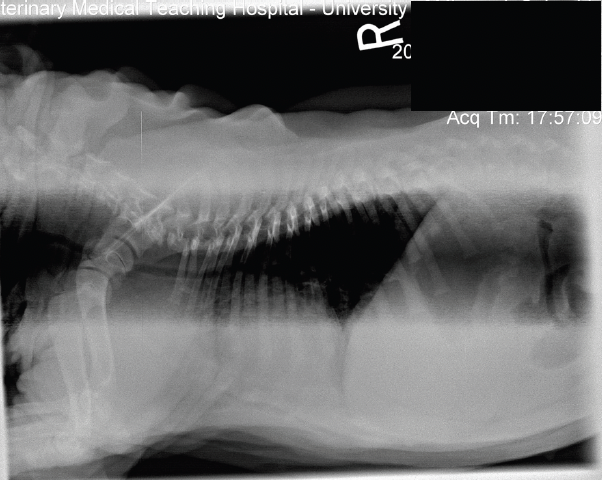

20

Q

Les techniciens en sueur vous présentent la RX suivante. Quelle décision prenez vous?

A. Faire l’interprétation de son mieux en expliquant au client nos limitations

B. Donner une sédation et reprendre la radiographie plus droite

C. Optez pour une contention manuelle et reprendre la radiographie plus droite

D. Reprendre la radiographie en doublant le mAs

A